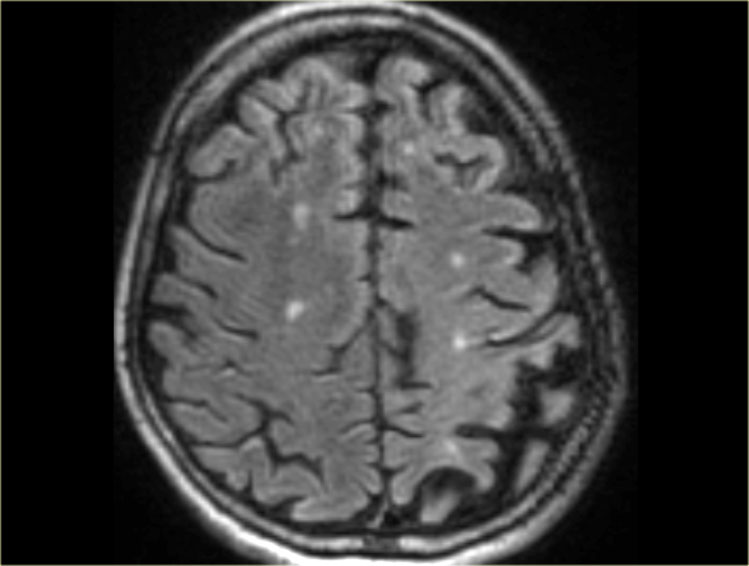

Dementia: According to the World Health Organization (WHO, 2024), dementia affects over 55 million people worldwide, with Alzheimer’s disease being the most common cause. Cognitive decline can be gradual, meaning some individuals may retain partial sanity for years.

Mild Dementia (Early Stage) – corresponds to an MMSE score in the range of 21–26

Moderate Dementia (Middle Stage) – corresponds to an MMSE score of 10–20.

Severe Dementia (Late Stage) – corresponds to an MMSE score below 10

[xiv] MMSE score, for example, denotes the severity of cognitive impairment as follows: mild Alzheimer’s disease: MMSE 21–26, moderate Alzheimer’s disease: MMSE 10–20, moderately severe Alzheimer’s disease: MMSE 10– 14, severe Alzheimer’s disease: MMSE less than 10. In clinical practice a variety of measures are used to assess disease severity, often in conjunction with clinically based assessments such as biographical interview.